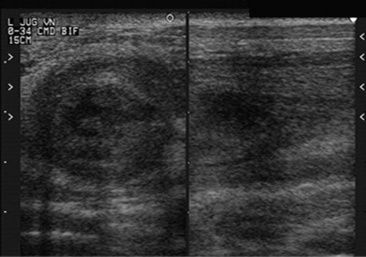

Aneurysms or pseudoaneurysms may be visualized radiographically as soft-tissue density masses continuous with a vessel wall (true aneurysm) or extending outward from a vessel wall (false aneurysm).203,204 However, the majority of the aneurysms involving the aorta and aortic root are not visible radiographically. Echocardiography is useful in the diagnosis of aneurysms involving the aortic root (Fig. 30-26).206-209 Angiography can be used in the diagnosis of peripheral vessel swelling or suspected thrombosis but is of little use in diagnosis of aneurysms of major vessels in adult animals. Ultrasonography may be used for the diagnosis of aneurysms or thrombosis of major arteries and peripheral vessels. In aortoiliac thrombosis of horses, ultrasound has been used to determine the origin of the thrombus and the extent of occlusion of the involved arteries (Fig. 30-27).218 Abdominal ultrasonography of the upper left flank dorsal to the left kidney has been used to diagnose aortoiliac thrombosis in calves.215 Diagnostic ultrasound has been used to detect thrombi in the caudal vena cava in cattle.219,220 Although the occluding thrombus is not imaged, the detection of a distended oval or round caudal vena cava, rather than the normal triangular vessel, in the eleventh and twelfth intercostal spaces is consistent with this diagnosis in cattle. Thrombi have been detected ultrasonographically in the hindlimb in both horses and cattle.221-224 Jugular vein thrombophlebitis has also been diagnosed ultrasonographically in both horses and cattle (Fig. 30-28).225,226 Similarly, diagnostic ultrasound has been used to image the cranial mesenteric artery, its branches, and the aorta in horses with verminous arteritis.227 Aneurysms appear as dilated vascular structures or vascular outpouchings continuous with the vessel wall,205 whereas a thrombus is apparent as a hypoechoic to echogenic mass within a blood vessel.226 Cavitation of an occlusive thrombus is suggestive of septic thrombophlebitis (see Fig. 30-28), whereas a nonseptic thrombus usually has a homogeneously hypoechoic to echoic appearance.226 Complete occlusion of the vessel can be determined ultrasonographically, or flow within an aneurysm or alongside a thrombus determined. Doppler ultrasound provides a more sophisticated method for determining blood flow and vessel patency. Computer-assisted radiographic techniques such as computed tomography and digital subtraction angiography may also be useful but have not yet been widely used in large animals. The latter methods may be limited in usefulness by the size of large animals and the cost of the equipment and procedures.

Fig. 30-28 Sonogram of the left jugular vein from a horse with septic thrombophlebitis. Note the cavitary appearance in the center of the thrombus consistent with infection.

In the case of catheter-associated thrombosis, a positive catheter tip culture (>103 colony-forming units), along with a positive blood culture, provides evidence of septic thrombophlebitis.228 An aseptic ultrasound-guided aspiration of the cavitary lesion within a heterogeneous thrombus can be performed, and the aspirate submitted for culture and sensitivity testing.226 Septic thrombophlebitis from any cause or embolic showering of septic thrombi may be accompanied by neutrophilic leukocytosis and elevation in fibrinogen concentration.